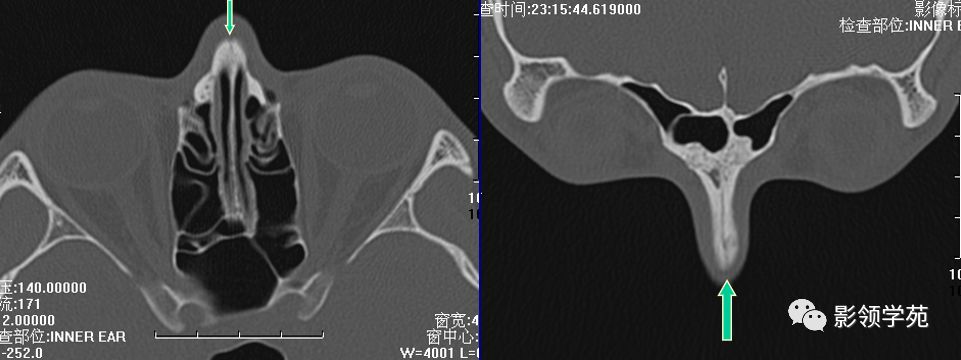

双侧鼻骨骨折

双侧上颌骨额突骨折

鼻中隔骨折